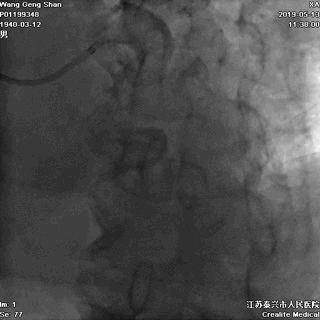

右头位定位

蜘蛛位定位

LCX球囊拘禁,主支支架释放

回撤LCX球囊

支架球囊再次扩张支架